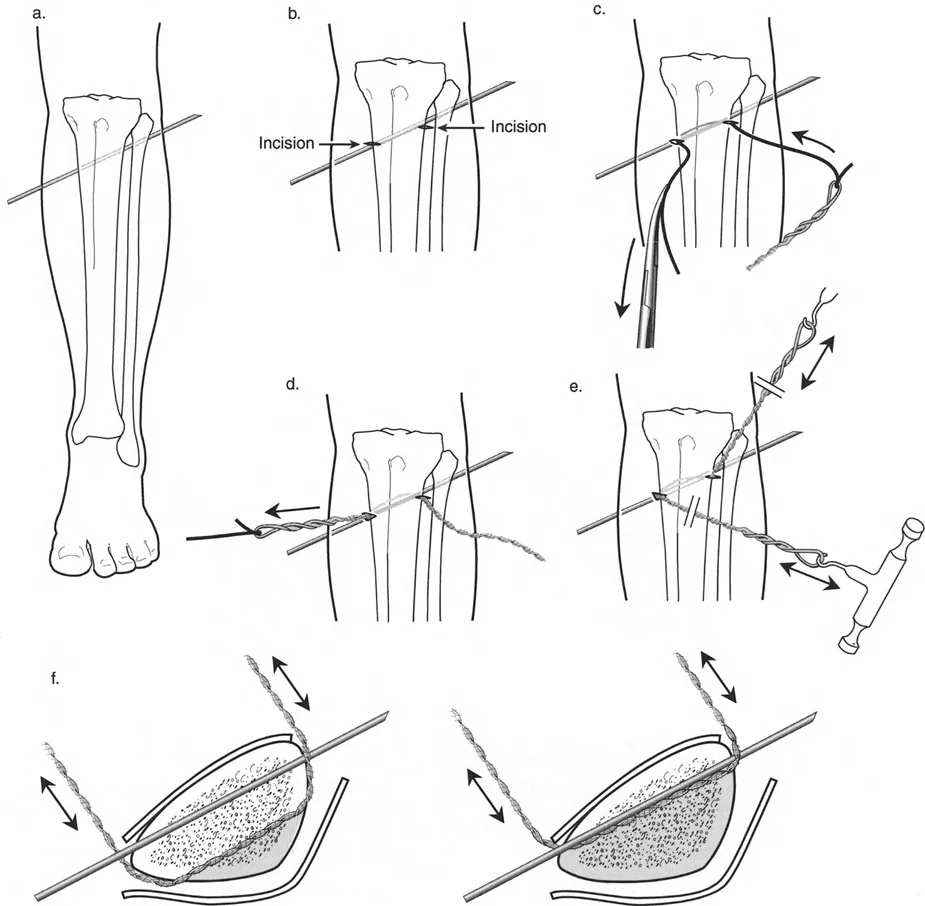

قيود الأسلاك والدبابيس في القاعدة 2

لتحقيق هذه الترجمة الضرورية والمقصودة بسلاسة باستخدام إطار دائري كامل الأسلاك، يلزم استخدام أسلاك الزيتون المعاكسة (counter-opposed olive wires). تعمل أسلاك الزيتون كقوى سحب ديناميكية، تسحب قطعة العظم على طول الحلقة أثناء فتح المفصلات. بدون أسلاك الزيتون، سيبقى العظم ثابتًا بينما تتحرك الحلقة عبر الأنسجة الرخوة، مما يسبب نخرًا شديدًا في الجلد.

على العكس من ذلك، إذا تم استخدام دبابيس نصفية (مسامير شانز)، فإنها تقيد العظم بطبيعتها بالحلقة. نظرًا لأن الدبابيس النصفية هي أذرع صلبة (مثبتة من طرف واحد بالحلقة ومغروسة في العظم من الطرف الآخر)، فإنها لا تسمح للعظم بالانزلاق على طول محور السلك. هذا يجعل أسلاك الزيتون غير ضرورية للترجمة في منشآت الدبابيس النصفية، ولكنه يتطلب من الجراح التأكد من أن الدبابيس النصفية قوية بما يكفي (عادةً دبابيس بقطر 5 مم أو 6 مم مطلية بهيدروكسي أباتيت) لتحمل لحظات الانحناء الناتجة عن الترجمة.

نصائح جراحية للمنشآت القريبة من المفصل

| المبدأ | التطبيق السريري | تحذير / خطأ محتمل |

|---|---|---|

| التحقق من CORA | دائمًا تحقق من CORA الحقيقي في الأشعة السينية الطويلة للطرفين قبل بناء المفصلة. | الاعتماد على الأشعة السينية القصيرة للركبة سيؤدي إلى CORA غير دقيق وبالتالي سوء محاذاة. |

| ACA العمودي | تأكد من أن محور المفصلة (ACA) عمودي تمامًا على مستوى التشوه. | محور ACA مائل سيحدث تشوهًا ثانويًا غير مرغوب فيه (مثل تصحيح التقوس ولكن إحداث الانحناء الأمامي). |

| تخليص الأنسجة الرخوة | عند استخدام قاعدة قطع العظم 2، احسب الترجمة المتوقعة وتأكد من أن الأنسجة الرخوة يمكن أن تستوعبها. | عدم مراعاة الترجمة يمكن أن يتسبب في اصطدام العظم بالجلد، مما يؤدي إلى النخر. |

| تقابل الأسلاك | استخدم ما لا يقل عن سلكين زيتون متقابلين لكل قطعة إذا كنت تتجنب الدبابيس النصفية. | الأسلاك الزيتون الفردية ستسبب قصًا ودورانًا غير مرغوب فيه حول محور السلك. |